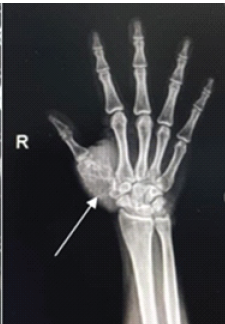

Chondromyxoid Fibroma of the Right Thumb: Successful Management with Wide Local Excision, Iliac Crest Bone Grafting and K-Wiring – A Rare Case Report

Ajit S Rathod , Jaideep Das , Sudhir Warrier , Santosh D Ghoti , Mohammed A Sohiel , Dharya H Pimpale

………………………………p.183-188